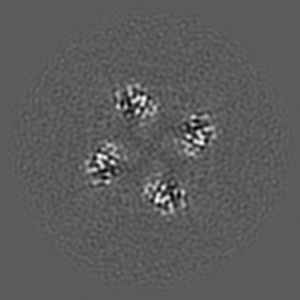

Inactivated-state cryo-EM structure of human TRPV3 in presence of tetrahydrocannabivarin (THCV) in cNW30 nanodiscs

Single-particle3.63 Å

Sample: full-length human TRPV3 in complex with THCV